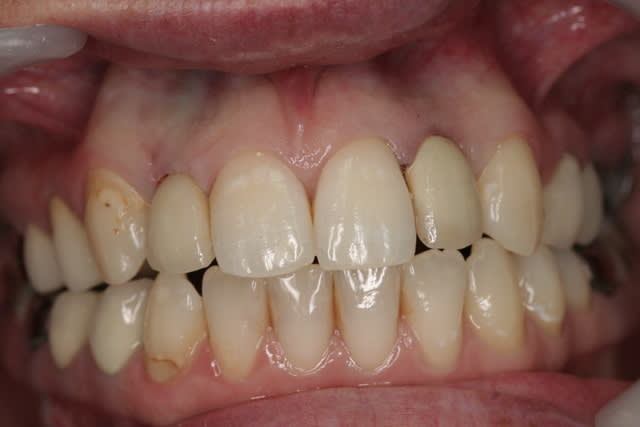

photos finish!!!

à noter...avec le flash...difficile de rendre le "naturel" de ces restaurations(teintes très claires)...après petite gingivoplastie pour harmoniser la hauteur des collets...(surtout pour 12...)